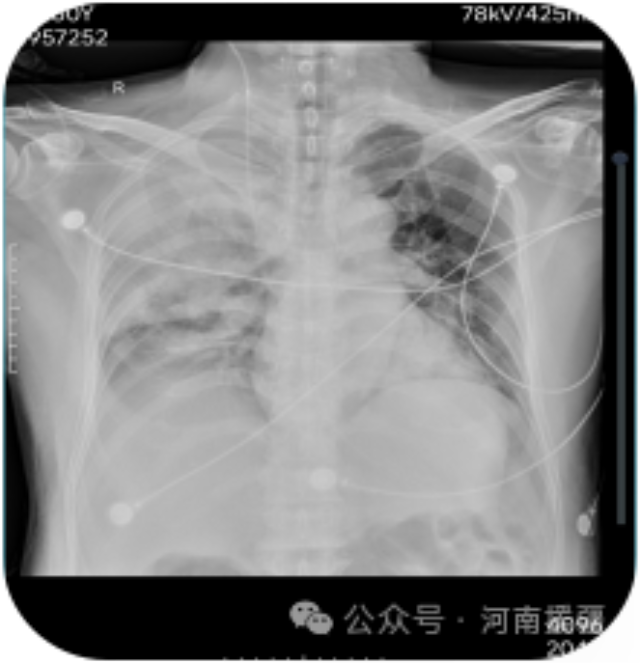

ECMO治疗前后患者胸部对比